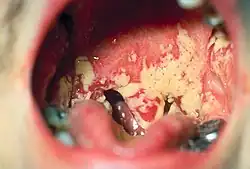

| Oral candidiasis patient showing characteristic white slough on the tongue. | |

It is characterized by a coating or individual patches of pseudomembranous white slough that can be easily wiped away to reveal erythematous (reddened), and sometimes minimally bleeding, mucosa beneath.[7] These areas of pseudomembrane are sometimes described as "curdled milk",[4] or "cottage cheese".[7] The white material is made up of debris, fibrin, and desquamated epithelium that has been invaded by yeast cells and hyphae that invade to the depth of the stratum spinosum.[4] As an erythematous surface is revealed beneath the pseudomembranes, some consider pseudomembranous candidiasis and erythematous candidiasis stages of the same entity.[4] Some sources state that if there is bleeding when the pseudomembrane is removed, then the mucosa has likely been affected by an underlying process such as lichen planus or chemotherapy.[5] Pseudomembraneous candidiasis can involve any part of the mouth, but usually it appears on the tongue, buccal mucosae or palate.[7]